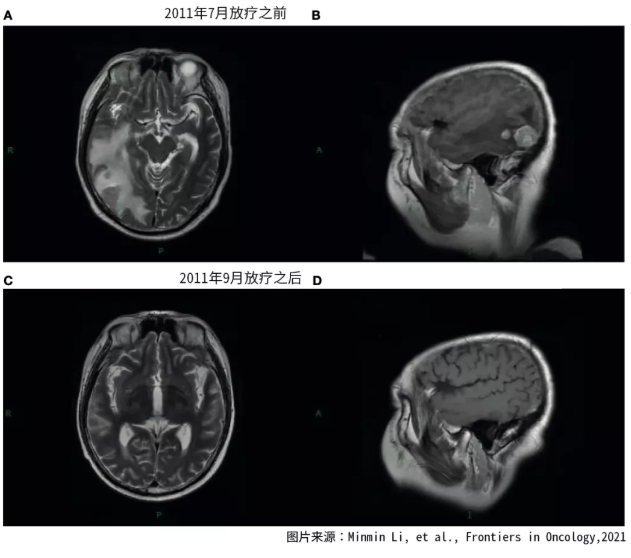

对脑转移的患者,放疗是最常用的治疗措施。对于多发性脑转移的患者,往往使用全脑放射治疗。但是由于放射的危害性,以及潜在的认知下降风险,全脑放射治疗往往只有一次机会,而且五年之内往往不能再次进行全脑放疗。因此,是否使用全脑放疗,什么时候使用全脑放疗,是一个困扰人的难题。 下面的这个案例报道中,患者接受了重复性的全脑放射治疗,获得了长达12年的生存期。最为重要的是,整个生存期内,患者的生活质量很好。 2006年5月,一名42岁的中国男性患者因为咳嗽、咳痰而就诊,纤维支气管镜检查显示左肺下叶部位有腺癌细胞。 磁共振MRI检查表明肿瘤已经转移到脑部。由于脑部有多个转移灶,不能使用伽马刀治疗。患者属于四期肺癌,也失去了手术治疗的机会,医生建议患者使用化疗联合放疗作为治疗措施。 图1. 2011年7月-9月放疗前后脑核磁检查结果 在进行了一个周期的吉西他滨联合顺铂的化疗后,对患者的原发病灶进行了放射治疗,使用的是二维放射治疗技术,总剂量为70格瑞,治疗分为35次。对脑部进行了全脑放射治疗,共20次分割,总放射剂量为40格瑞。 放疗之后,患者接受了三个周期的化疗,化疗用药为紫杉醇和顺铂。经过这些治疗,患者的症状明显减轻,血液的肿瘤标志物明显下降。放疗后的肿瘤病灶被评估为完全缓解(可见肿瘤病灶消失)。这种情况持续了近五年时间。 2011年7月,患者因为脑部转移瘤复发而入院,患者表现为意识障碍。PET-CT扫描显示脑外的肿瘤病灶稳定。 图2. 2016年1月脑放疗之前的核磁结果 患者每天使用150毫克的厄洛替尼进行治疗,同时使用三维放射治疗,再次进行了全脑放射治疗。总剂量为30个格瑞,分15次完成。放疗完成之后,患者进行了四个周期的尼莫司汀和厄洛替尼的维持治疗。2011年9月,脑部核磁发现转移灶显著缩小,患者的病情得到了有效控制。 2016年1月,时隔近五年,患者出现了病情进展的迹象。医生使用18毫米准直器对患者的脑单病灶进行了放疗,放疗靶区中心剂量为25.4格瑞,治疗评估为部分缓解。但是3个月之后,出现了新的脑部病灶。由于放疗后短时间内复发,因此选择了尼莫司汀化疗,治疗时间为四周,作为姑息治疗方式。由于后期反复的肺部感染严重影响了患者的健康, 患者于2018年8月不幸因呼吸衰竭而去世。 图3.2016年4月放疗之后再次出现脑进展 尽管在治疗期间进行了多次放射治疗,但是患者的生活质量良好,即使进行了二次全脑放射治疗,也没有出现严重的神经认知缺陷和其他严重的不良反应。 启示 回顾这名患者的治疗过程,曲折而又艰难。不断反复出现的脑转移灶,让患者不得不经受两次全脑放疗。万幸患者在治疗后,得到了有质量的生存期。 医生在制定治疗方案时,需要根据患者的整体情况,考虑放疗的剂量,部位等等,这需要医生具备专业的知识技能和丰富的临床经验。否则,同样的放疗,同样的设备,治疗效果也有可能会出现差异。 本案例中患者的驱动基因状态我们无法得知,如果有可能,也许可以通过入脑效果好的靶向药物治疗,这样对患者的脑部病灶进行一些控制,从而减少脑放疗的次数和剂量,患者可能会因此受益更多。 参考文献: Minmin Li, et al., Reirradiation of Whole Brain for Recurrent Brain Metastases:A Case Report of Lung Cancer With 12-Year Survival, Frontiers in Oncology,2021晚期脑转移肺癌患者的抗癌历程